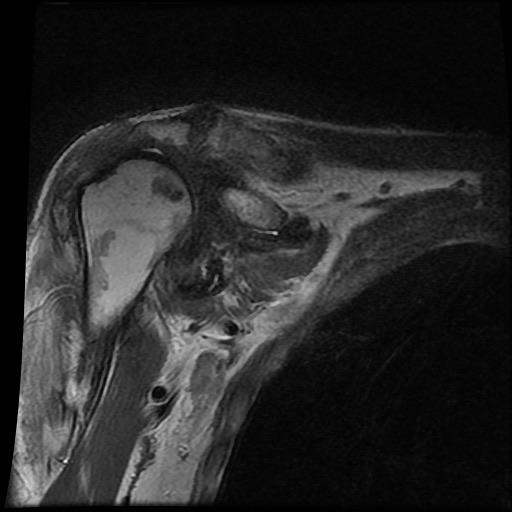

Tiếp tục xem hình ảnh MRI của bệnh nhân này.

Hình ảnh MRI:

Tràn dịch lan tỏa tất cả các khớp cổ tay.

Phù tủy xương lan tỏa tất cả các xương cổ tay.

Bào mòn xương, ví dụ tại xương thuyền, xương đầu và xương móc.

Phá hủy khe khớp và sụn khớp, rõ nhất tại khớp STT và CMC4/5.